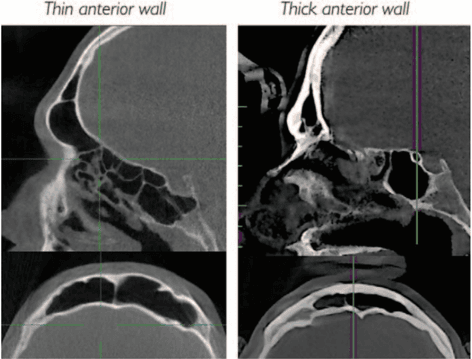

Micro Fractured and Purified Adipose Tissue Graft (Lipogems®) Can Improve the Orthognathic Surgery Outcomes Both Aesthetically and in Postoperative Healing

M. Raffaini, C. Tremolada, CellR4, 2014